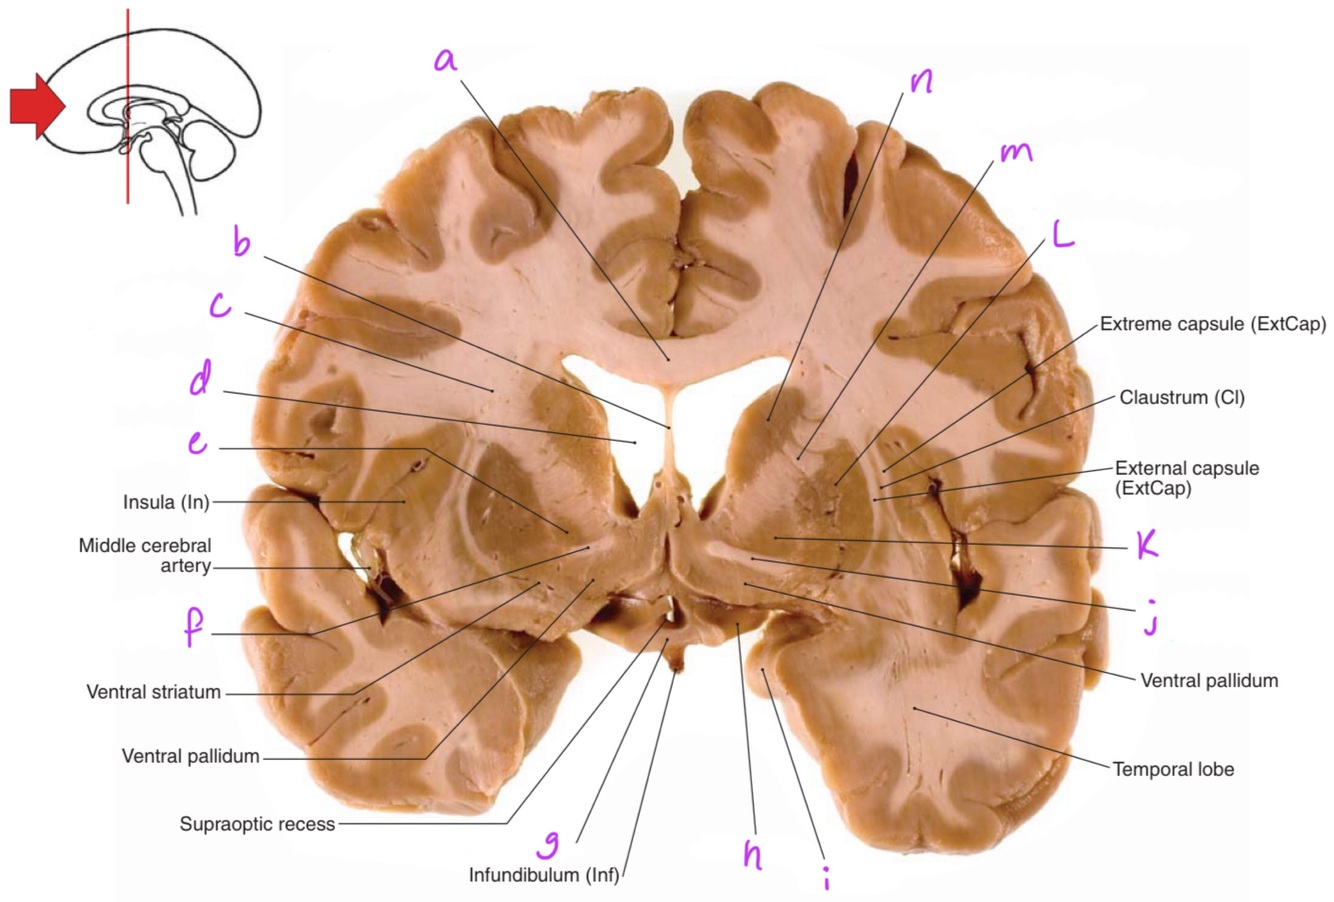

a

Body of corpus callosum

b

septum pellucidum

c

Corona radiata

d

Anterior horn of lateral ventricle

e

Globus pallidus

f

Anterior commissure

g

Optic chiasm

h

Optic tract

i

Uncus

j

k

L

Putamen

m

Anterior limb of internal capsule

n

Head of caudate nucleus